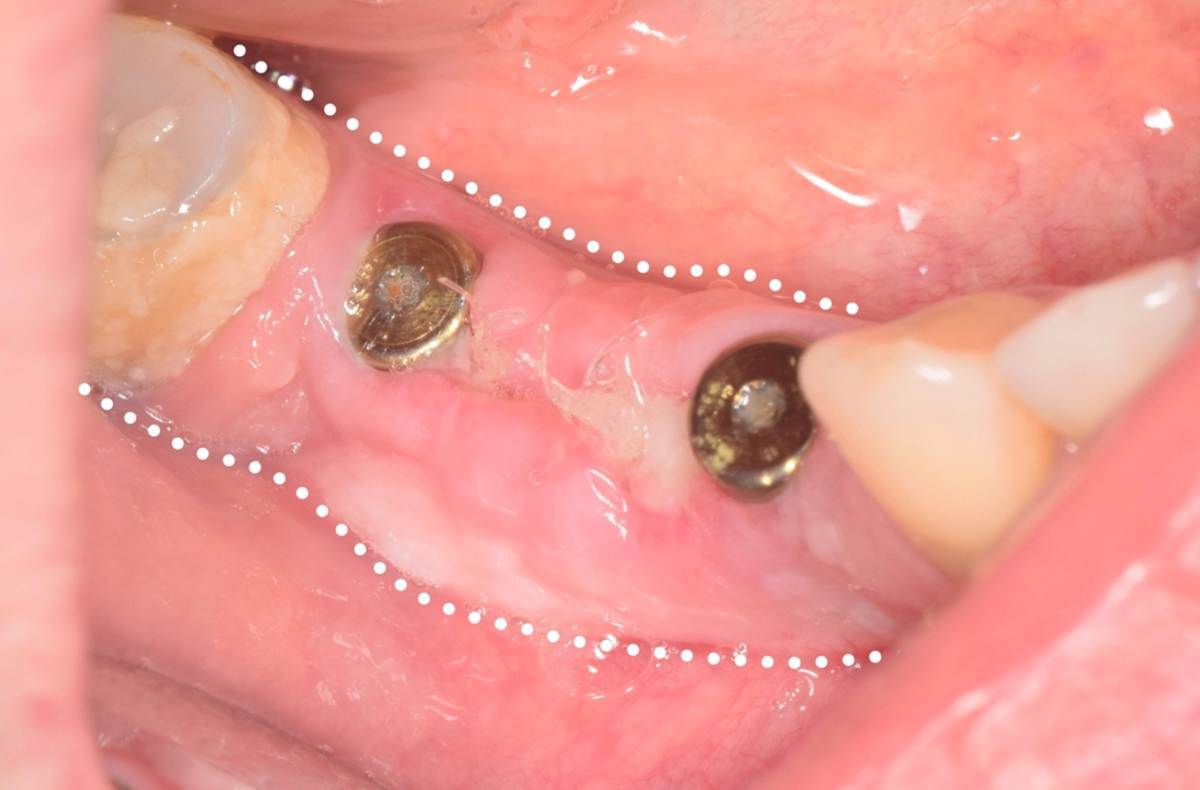

Fin Опубликовано 5 июня, 2025 Поделиться Опубликовано 5 июня, 2025 Здравствуйте коллеги. Хотел бы представить вашему вниманию первую часть кейса по восстановлению 4 сегмента. Перелом зуба 4.5 под мостовидным протезом 4.7-4.4. 4.7 решено оставить до последующего повторного протезирования При планировании имплантации вестибулярное оголение имплантата на 1.5-2мм в области 3. 4. Дефицит керотинизированной слизистой оболочки. Более глубокое положение имплантата приведет к чрезмерному количеству сзизистой оболочки в 7-8 мм. Решено не пытаться использовать ССТ с целью перекрытия оголенного имплантата а попробовать технику морковки профессора Кюри. 1 этап операции. Удаление зуба 4.5, подготовка костного ложа под имплантаты при помощи трепанов и запор костных морковок, установка имплантатов неодент 3.75х10 в позицию 4.4, 4.3х10 в позицию 4.6, ушивание. 2 этап. Создание прикрепленной слизистой. Расщепление лоскута, удаление пиноа, пересадка СДТ с фиксаций его этими же пинами. 3 этап. Открытие имплантатов с установкой ФДМ и снятие швов через 2 недели. Решил не добавлять ССТ. На данный момент ожидаем полное восстановление тканей и приступаем к этапу протезирования. Так как параллельность имплантов достаточна планирую протезировать с уровня имплантатов. 3 2 1 Ссылка на комментарий